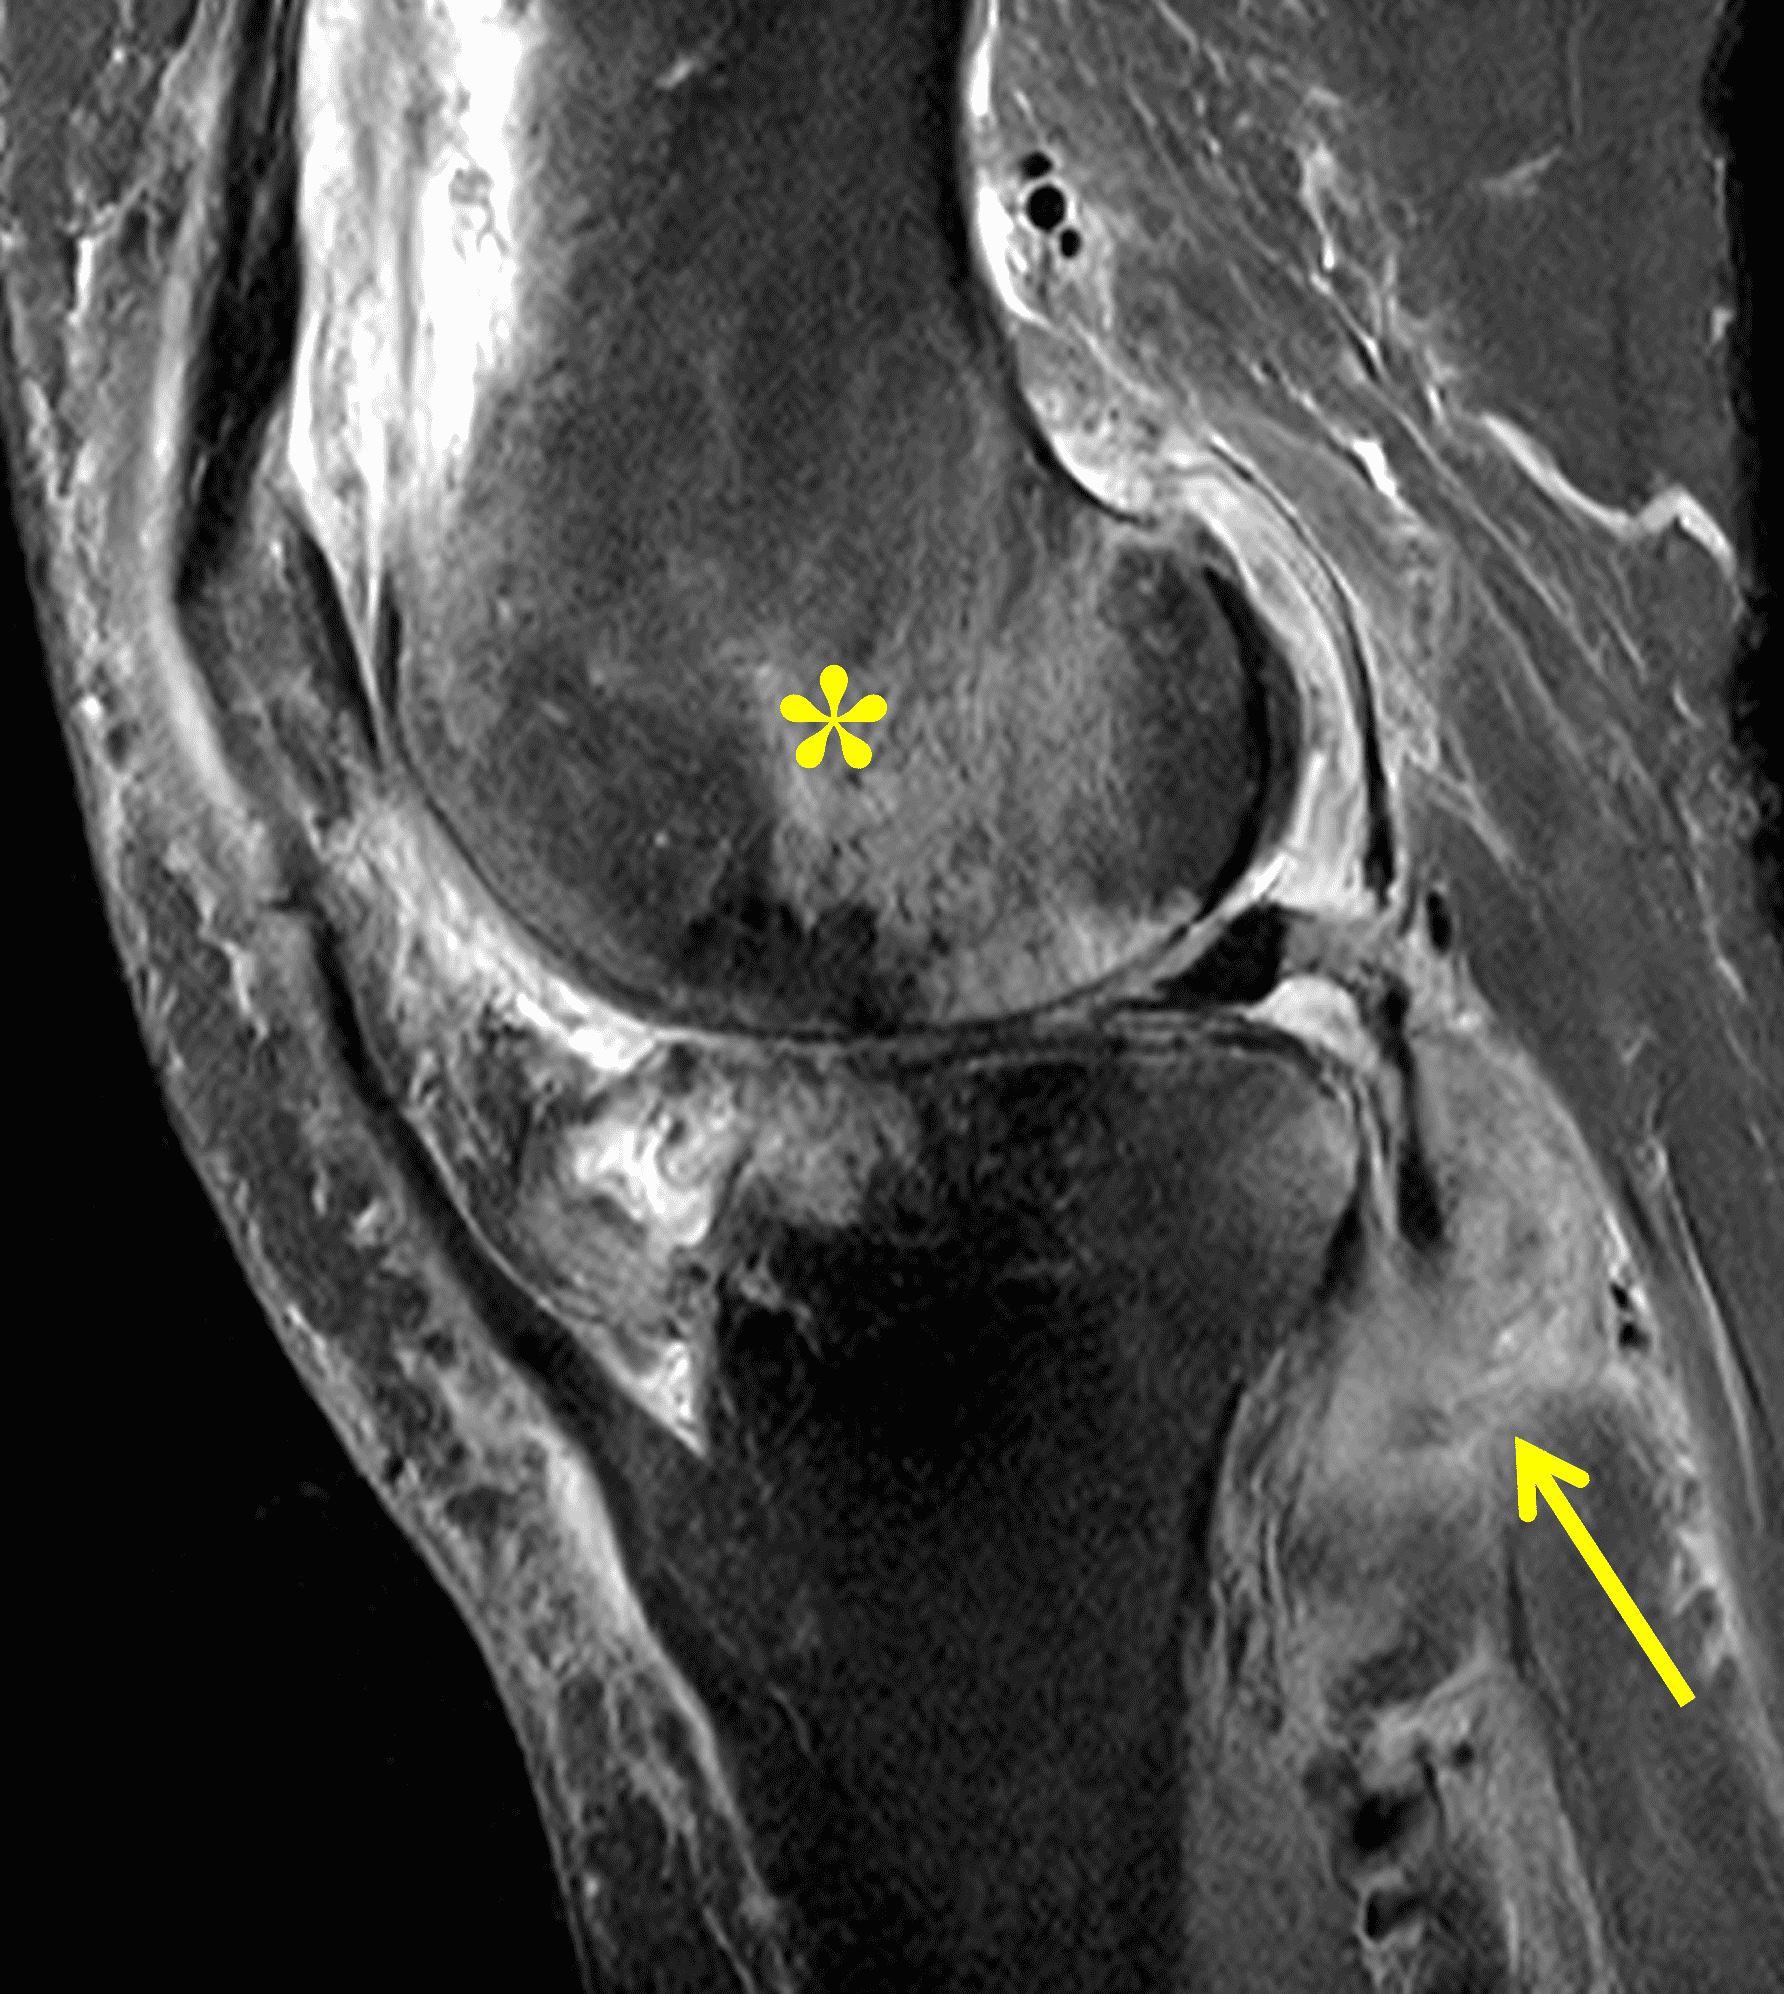

Figure 2: (2A) The coronal image shows a large effusion and severe hypertrophic synovitis (asterisks) in the knee. (2B) On the sagittal image the hypertrophic synovium (asterisks) involves the suprapatellar and infrapatellar recesses as well as the anterior and posterior intercondylar notch. A reactive lymph node (arrow) is present in the popliteal fossa. (2C) The axial image demonstrates myositis (arrows) involving the popliteus and peroneus longus muscles. Note the preserved articular cartilage, lack of erosions, and the absence of subcutaneous or marrow edema.